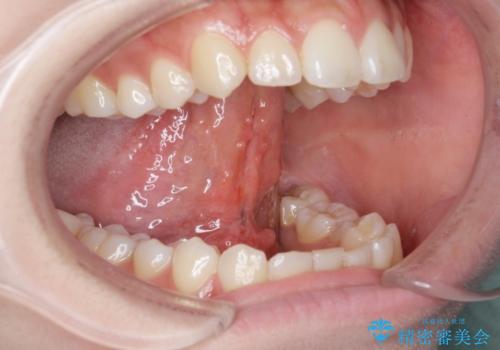

[ 舌小帯の形成 ] 滑舌を改善したい

担当医 大元洋佑

![[ 舌小帯の形成 ] 滑舌を改善したいの症例 治療前](https://seimitsushinbi.jp/wp/wp-content/uploads/2022/10/fa797540f242dace21c05a8161580df4-500x350.jpg?v=1665555891)

![[ 舌小帯の形成 ] 滑舌を改善したいの症例 治療後](https://seimitsushinbi.jp/wp/wp-content/uploads/2022/10/45c8c51b664db205e71949fb1e2ec432-500x350.jpg?v=1665555859)